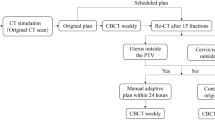

The planning objectives were identical for both dynamic IMRT and VMAT planning. The dose was prescribed to PTV, in accordance with the recommendations of the International Commission on Radiation Units and Measurements 83 report [17]. The prescribed dose was 50.4 Gy in all patients, delivered in daily fractions of 1.8 Gy. The dose was prescribed to cover 95% and 100% of the PTV and CTV, respectively. Care was taken to maintain a difference of < 10% between the prescribed and maximum doses. Axial CT scan slice representations of a patient planned with C-IMRT (A), A-IMRT (B) and VMAT (C) were shown in Fig. 1.